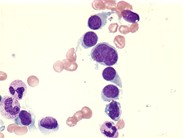

Hairy cells - 1.

Category: Lymphoma: Mature B-cell and Plasma cell Neoplasms > Splenic lymphomas > Hairy Cell Leukemia

The classic appearance of the hairy cell has elongated cytoplasmic projections distributed around the circumference of the cell.